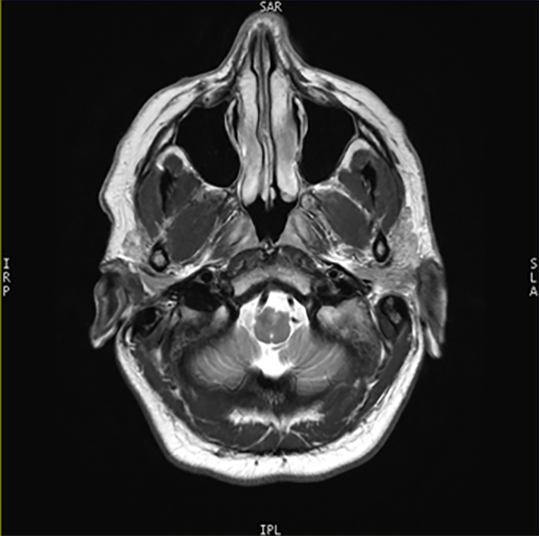

Understanding slice orientation and image annotations

The Viewer includes coordinate annotations that explain the orientation of the subject when the scan captured the image.

You can combine these abbreviations to understand precisely how the subject was oriented in three planes.

In this image, the annotations explain that the image was obtained with the following orientations:

| Top | SAR | Superior, anterior, right orientation |

| Right | SLA | Superior, left, anterior orientation |

| Bottom | IPL | Inferior, posterior, left orientation |

| Left | IRP | Inferior, right, posterior orientation |